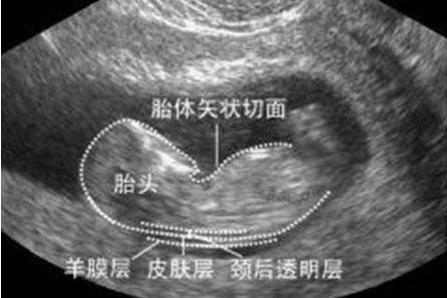

在孕期11~14周之间做的检查,早唐+NT其实是两项不同的检查,早唐是抽血检查,而NT是B超检查,之所以合并在一起,是因为检查的时间非常相近。

这次检查一定要在孕期14周前完成,否则胎儿颈部透明带消失,就无法进行检查了。

孕妈在NT检查前可以带一些食物,因为NT检查需要胎儿呈现特定的姿势才能看清,在检查中适当进食,可以促进胎儿移动,帮助调整最佳的姿势。